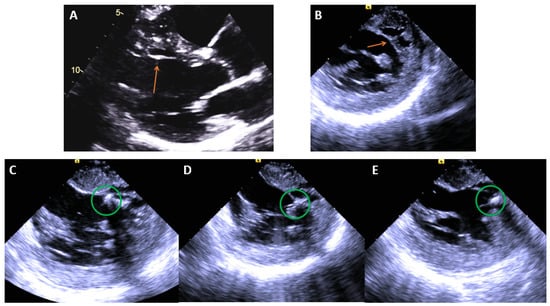

5. Papillary Muscle VT

5.1. ECG Signatures

5.2. Catheter Ablation Considerations